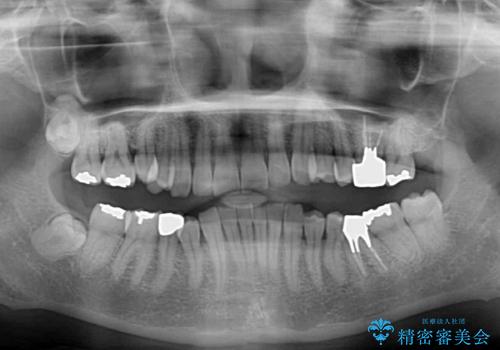

- 奥歯が咬めないくらいに痛いとのことで来院された患者様です。

痛みの強い歯は、歯髄組織が強い炎症を起こしており、神経を取り除く必要であったため、速やかに根管治療を行いました。

その後、オールセラミッククラウンにて補綴治療を行う予定でしたが、処置した歯以外にも治療が必要と思われる歯があったり、デコボコした歯列も気になるとのことで、患者様希望によりインビザラインにてマウスピース矯正を行うこととしました。

まずは矯正治療前に必要なむし歯処置を行い、その後矯正治療を行ってから、最後にオールセラミッククラウンなどで補綴治療を行うこととしました。

咬合力が非常に強く、全体的に歯が擦り減っている状態であったので、理想的な咬み合わせを達成することは難しく、また咬合力が強い方のマウスピース矯正は、思い通りに動かないことがあるため、ワイヤー矯正の方が望ましいように思えました。